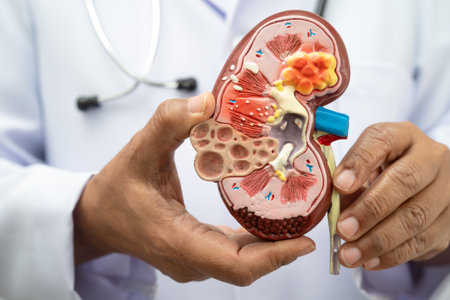

Kidney disease, Chronic kidney disease ckd, Doctor hold human model to treat and study in hospital.

Detailed model of a human kidney held in a hand for educational purposes in a neutral setting

Kidney disease, Chronic kidney disease ckd, Doctor hold human model to treat and study in hospital.

Model of human kidney held in a hand showcasing internal structure and details for educational purposes